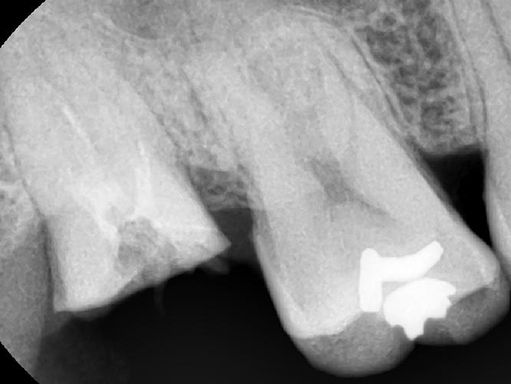

안녕하세요 목동안치과 안상우 원장입니다오늘은 뿌리만 남은치아를 살리는 방법에 대해서 알아볼꺼에요치아의 뿌리는 턱뼈에 고정이 되어 치아의 머리부위가 물리게 되서 음식을 저작하게 됩니다.그런데 치아가 외부충격이나 충치등으로 인해서 머리부위가 상실되게 되면 치아의 기능을 할수 없게 됩니다. 이런경우 치아가 없어진것 같아 보일수 있지만 실제적으로는 잇몸안에 뿌리가 남아 있는 경우가 많이 있어요.이런경 우에는 발치를 하지 않고 치아를 살릴 수 있는 방법이 있습니다.치과에서는 post라고 하는 치료 방법이 있습니다.post란 기둥을 의미하는 데요 치아에 기둥을 세우는 것이에요.부러진 치아에 기둥을 어떻게 세우냐고 하실수도 있습니다.치아 안 에는 신경이 있는 신경관이 있어요.파절이나 충치로 인해서 치아의 머리부위가 손상이 되었다면 신경관이 노출되게 됩니다.이렇게 노출된 신경관을 신경치료를 통해서 깨끗하게 청소를 하고 이후에 이 신경관에 기둥을 세우는 거에요.사진은 post 치료를 하는 과정입니다.신경관을 깨끗하게 정리 한 다음에 안쪽을 세척을 하게 됩니다.그 다음에 포스트와 치과용 시멘트를 이용해 뿌리부분이 머리 부분의 힘을 지탱할수 있도록 해줍니다.이후에 머리에 레진으로 수복을 하고 머리와 뿌리부분이 연결되도 하는 치료방법입니다치아에 들어가는 포스트 재료는 치아와 탄성이 거의 같은 fiber post를 사용하게 됩니다이렇게 되면 부러졌던 치아의 머리가 뿌리와 잘 결합이 되어 저작력을 지탱해 주게 됨으로써 치아의 기능을 할 수 있게 됩니다.결과적으로 없어진 것으로 생각했던 치아를 사용할 수 있게 된것이지요포스트 치료는 상실된 치아를 살려서 다시 사용할 수 있게 하는 좋은 치료방법입니다.하지만 포스트 치료를 하지 못하는 경우도 있습니다.치아가 파절이나 충치가 생겼을 때 손상된 부위가 잇몸뼈 아래로 진행이 되어 있게 되면 포스트 치료를 할 수 없어요.또한 포스트를 이용해서 치아를 살려도 교합력이 너무 강해서 제작한 기둥이 교합력을 정상적으로 버티지 못하는 경우도 있어요.보통 남성분들이 교합력이 강한 경우가 많은데요 이런 경우에도 포스트를 하기 힘들 수도 있어요하지만 치아를 발치하기 전에 포스트치료의 가능성에 대해서 알아보는 것은 치아를 보존할 수 있는 길이기도 합니다.치아는 한번 발치하면 이전 상태로 돌아가기 어렵기 때문이에요.